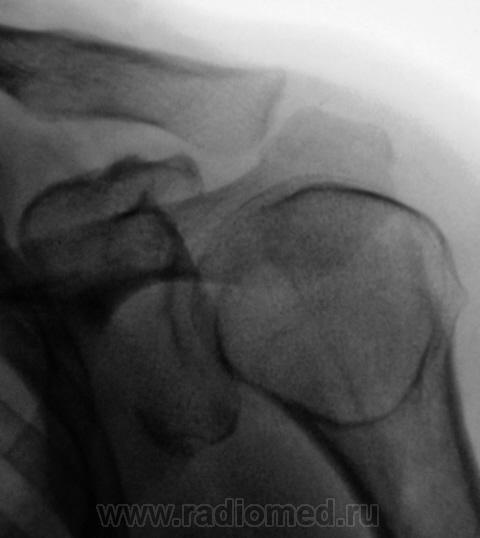

Травма. Пациент направлен на рентгенографию плечевого сустава.

Травма.  Пациент направлен врачом хирургом на рентгенографию плечевого сустава. Ваше мнение уважаемые коллеги?

Здравствуйте! Начальный деф артроз в плечевом суставе со стороны лопатки. Из- за неправильной укладки в головке плеча - кажется, что киста, на самом деле - норма. Перелом акромиона сомнителен...

О кисте совершенно не думал, но 1 и 2 (левые) снимки, укладка-то стандартная, вот правые два, так те с "поворотом".

Не дает покоя линейная тень в метаэпифизе плеч. кости, продолжается на диафиз.Никогда не видел таких переломов. Метафиз поротичный.

Плечева кость развернута-межбугорковая борозда.

Добрый вечер Валентин Львович! На представленном Вами снимке контуры большого бугорка идут по наружному краю а противоположно малый бугорок, если я не прав поправте меня. А пациент старше 40 лет?

Лично я не вижу свежих костно-травматических изменений  и написал бы именно так.

А пациент "плачет", к облсти плечевого сустава не дает прикоснуться, говорит, что сильно больно, а хирург спрашивает - "А подвывих есть?"

Для полного исключения подвывиха и вывиха(а может быть и задний),  лучше сделать транстаракальный снимок плечевого сустава.

В данном случае несколько слерозирован малый бугорок.

Валентин Львович, у меня вопросы по первым (верхним) снимкам:

1. На двух правых снимках как вы объясняете довольно четко ограниченное разрежение структуры (криво обведено мною красной линией)?

2. Вас не смущает причудливая форма клювовидного отростка на двух левых снимках?

1. На двух левых снимках, то, что могло показаться "кистой" - желтые стрелки, действительно, как отметил Анатолий Владимирович, конечно никакая не киста, и укладка в данном случае "не виновата". Просто, головка в результате подвывиха олказалась несколько ротированной, что и поменяло "привычную картину". Мы довольно часть встречаемся с таким феноменом при подвывихах головки плечевой кости.

2. Конечно, пациент, в присутствии врача хирурга был взят за экран. В принципе все вопросы были решены, но коллега попросил сделать снимок " с поворотом" - это два правые снимка.

3. Вы соверошенно правы, Татьяна Валентиновна, что два участка в области проксимального эпи-метафиза плечевой кости несколько "поротичны", может возраст? За экраном крутили, весьма пристально, но вроде-бы глаз ни за что не зацепился.

4. Клювовидный "не нормальным" не показался. А Вы что-то заметили?

В том-то и дело, Валентин Львович, что если на двух левых снимках, выполненых при ротации плеча вследствии подвывиха, головка плечевой кости находится в ортогональной проекции и на снимке дает известный скиалогический эффект в виде кольцевидной склерозированой тени и разрежения структуры (такой же эффект на двух правых снимках в виде разрежения структуры в зоне большого бугорка), то на двух правых снимках, которые проекционно ближе к стандарту (большой бугорок практически на контуре) отмеченого мной разрежения структуры в норме быть не должно. Поэтому, очень рекомендую МРТ, КТ, хотя бы "возьмите пациента на конроль"

Что касается клювовидного отростка: он какой-то странной формы, как-бы двойной. Может, конечно, он таким уродился, а может и сломался. Я бы сделала снимки двух суставов в максимально одинаковых проекциях.

здесь вывиха в АКС? На мой взгляд акромиальный конец ключицы несколько приподнят?